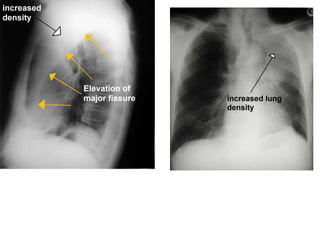

LOBAR ATELECTASIS

Radiologic signs of lobar atelectasis :- Direct

or Indirect .

Direct signs include increased opacification

of the airless lobe and displacement of

fissures.

Indirect signs include displacement of hilar and

cardiomediastinal structures toward the side of

collapse, narrowing of the ipsilateral intercostal

spaces, elevation of the ipsilateral

hemidiaphragm, compensatory hyperinflation

and hyperlucency of the remaining aerated

lung, and obscuration or desilhouetting of the

structures adjacent to the collapsed lung

(eg, diaphragm and heart borders). Additional

radiologic features vary according to the site of

atelectasis.